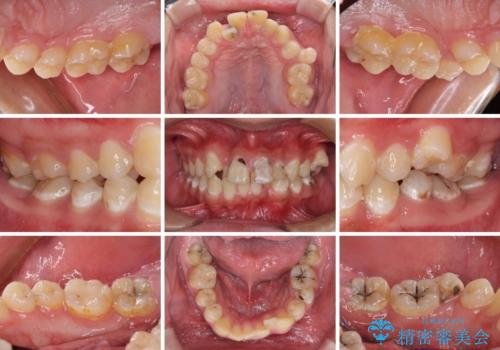

- 10代男性(高校生)

- むし歯が多く、歯並びも悪いとのことで、以前通院されていたご家族の紹介で来院された患者様です。

口腔内に無頓着であったため、まずはしっかりと歯磨きトレーニングを行い、必要な虫歯治療を行いました。

矯正治療は、むし歯が酷く抜歯が望ましい歯を1本抜歯して、ワイヤー装置にて整えることとしました。